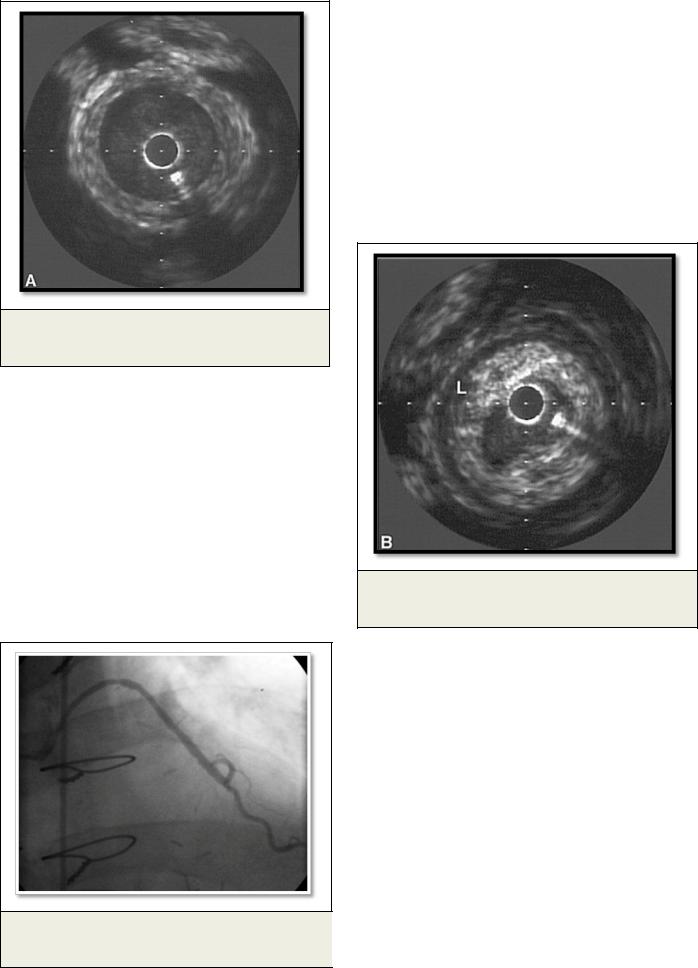

Рис. 3. Внутрисосудистый ультразвук.

Гиперплазия интимы венозного шунта.

Другой значимой причиной поражения венозных шунтов является гиперплазия интимы (Рис. 3) за счет увеличения количества клеток гладкой мускулатуры и внеклеточного матрикса, возникающая в период от 1 месяца до 1 года после операции.

Рис. 4. Внутрисосудистый ультразвук.

Концентрическая атеросклеротическая бляшка.